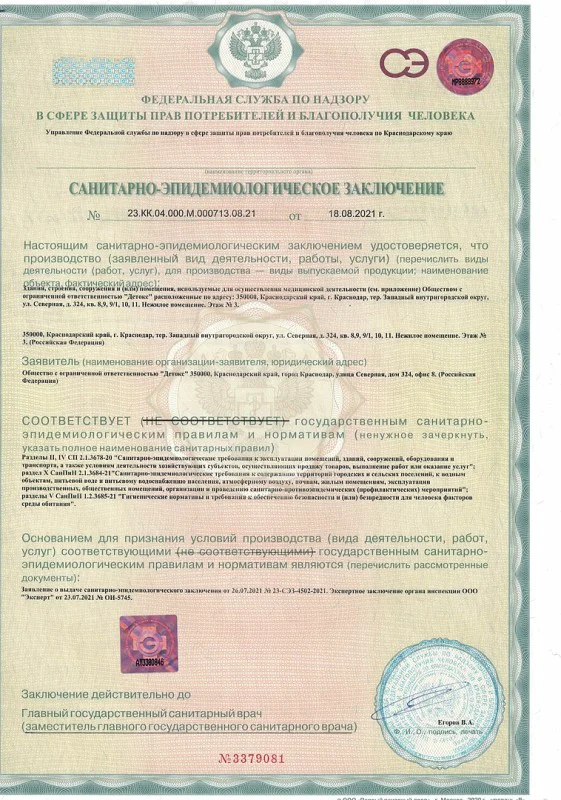

Лицензия на осуществление медицинской деятельности

Лицензия на осуществление медицинской деятельности

Лицензия на осуществление медицинской деятельности

Лицензия на осуществление медицинской деятельности

Лицензия на осуществление медицинской деятельности

Лицензия на осуществление медицинской деятельности

Лицензия на осуществление медицинской деятельности

Лицензия на осуществление медицинской деятельности